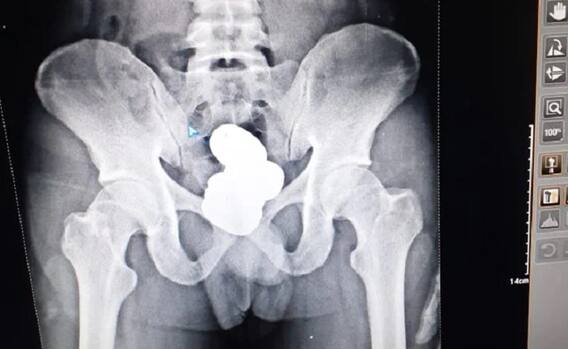

सोने की तस्करी में पकड़ा गया आरोपी इंफाल से दिल्ली जाने वाला था. उसने करीबन 900 ग्राम वजनी सोना का पेस्ट अपने पेट के मलाशय में छिपाया था. जांच के बाद पुलिस ने यात्री की तलाशी ली तलाशी के दौरान की सीआईएसएफ और कस्टम के अधिकारियों ने उसके मलाशय में करीब 908.68 ग्राम के वजन का गोल्ड पेस्ट के चार पैकट दिखे.

इसके बाद अधिकारियों ने उसका मेडिकल करने के लिए ले गए जहां उसके शरीर के निचले भाग का एक्स-रे किया गया. एक्स-रे में यात्री के मलाशय में गोल्ड पेस्ट देख सब दंग रह गए. गोल्ड पेस्ट का पता लगने के बाद यात्री ने अपने आरोप कबूल कर लिए. बाद में यात्री को आगे की कार्रवाई के लिए कस्टम व सीआईएसएफ को आगे सौंप दिया गया.